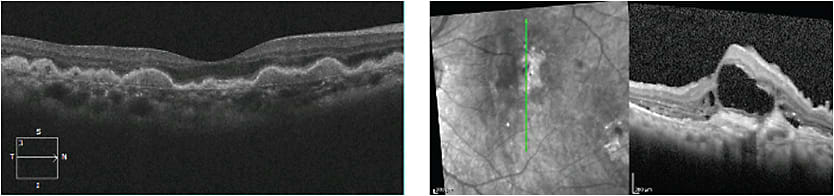

In patients with diabetes, macular OCT can help diagnose diabetic macular edema (DME), even in patients whose clinically significant macula edema (CSME) is not readily visible on slit lamp biomicroscopy (Figure 6).

Figure 6. OCT of diabetic macular edema.

Once you diagnose DME, early referral to a retina specialist is important so treatment can be initiated promptly. The armamentarium for treating DME is growing and includes intravitreal injections of anti-vascular endothelial growth factor (VEGF) (ranibizumab, Genentech; bevacizumab, Genentech; and aflibercept, Eylea), and intravitreal injections of triamcinolone acetonide, dexamethasone and fluocinolone acetonide, as well as combination or solo therapy with focal laser or micro-pulse laser, or both.

NO SOLO ACTS

Do not rely solely on macular OCT when examining patients with diabetes, especially in those patients who have long-standing disease and/or poor glycemic control. Such patients occasionally present with excellent visual acuity and without OCT-based evidence of diabetic macular edema. However, some patients may have proliferative diabetic retinopathy with peripheral neovascularization that the physician can be miss unless they are given a complete exam with dilation, and examination of the peripheral retina, combined with fluorescein angiography — preferably with widefield or ultra-wide fluorescein angiography (Figure 7).

Figure 7. Top: OCT of patient with proliferative diabetic retinopathy without diabetic macular edema. Bottom: Ultra-widefield fluorescein angiography of same patient revealing proliferative neovascularization.